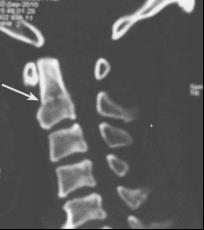

家住霍邱县高塘镇的张奶奶在家行走时不慎摔伤,致颈部疼痛、无法活动,被送至我院就诊。完善相关检查诊断为“第2颈椎(枢椎)齿状突骨折”,因伤情严重,经患者和家属同意在我院行手术治疗。

如果X线摄片难以确定有否齿突骨折,可以做枢椎 CT或WR-3D,以齿突为中心的冠状和矢状面重建CT、WR-3D可以证实平片上的可疑影像。CT、WR-3D比X线影像可以提供更多的信息但也容易因为成像质量的问题而产生误导,造成误诊。患者如果没有神经损伤就不必做 MRI检查在中矢面重建CT和MRI影像上见到的软骨结合(synchondrosis)残迹容易被误认为是齿突的骨折线。

图2 齿突骨折